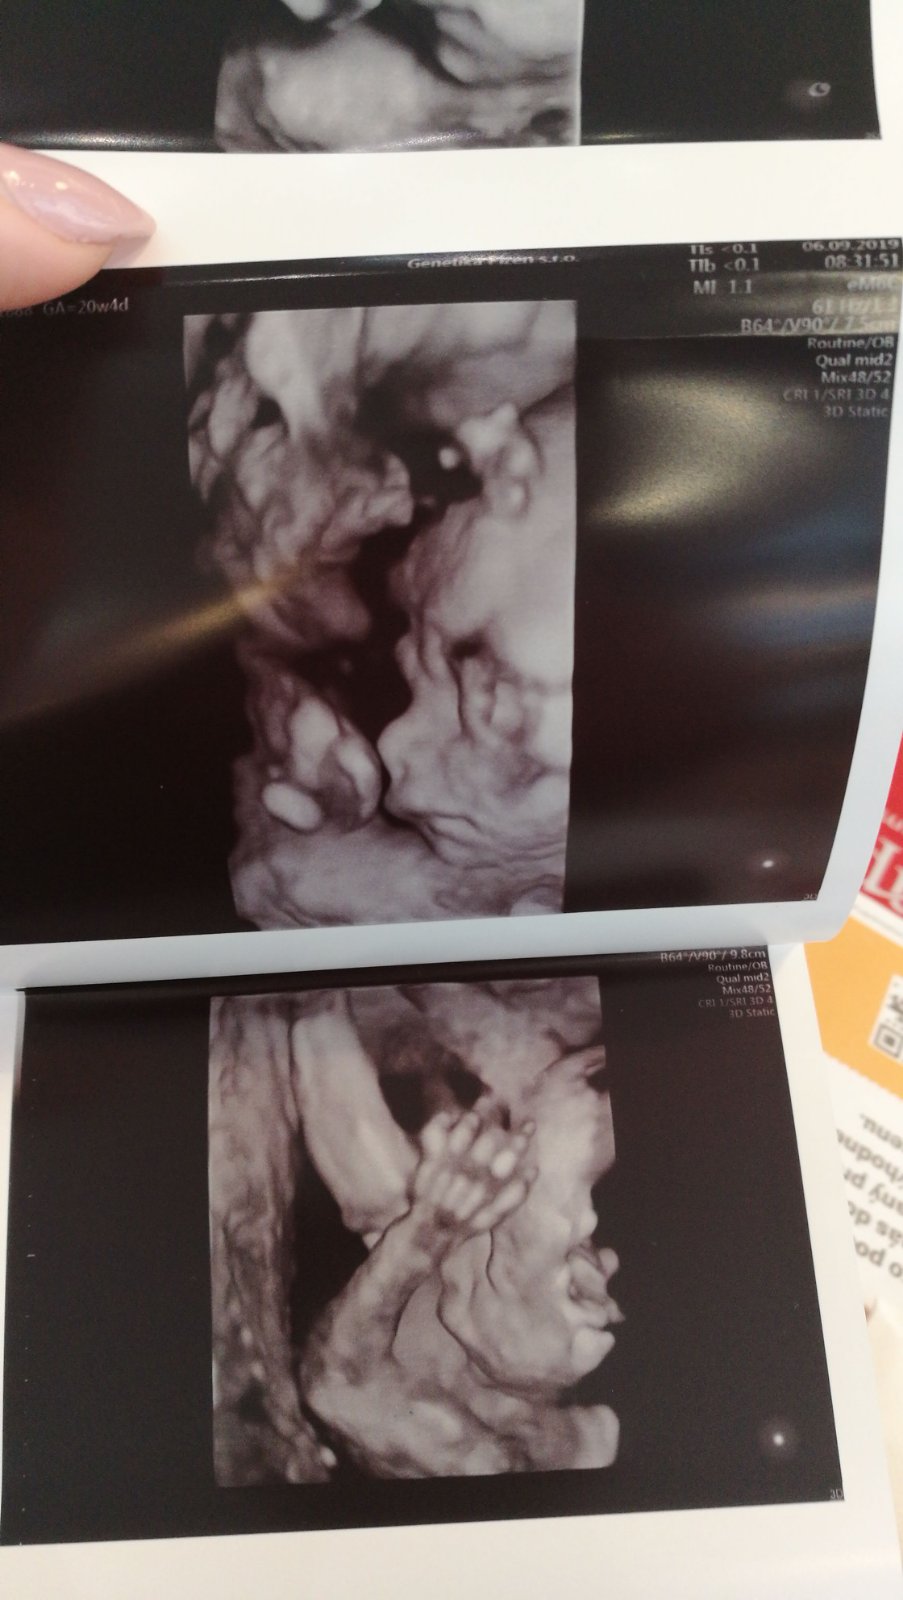

Ahoj holky, tak my máme 2. screening za sebou, byli jsme včera. Vše je v naprostém pořádku a na svém místě, vše funguje tak, jak má, opět potvrzena holčička a bylo super ji opět vidět 🙂 Pán doktor ultrazvuk přepnul na chvíli i na 3D a je to mazec vidět už ty rysy obličejíčku 🙂 Jinak my chodíme do Brna do Prenatalu, platili jsme 1200 Kč a dostali jsme 3D fotečku a nahrávku celého ultrazvuku na CD. Tak pak pisnite váš zážitek 😇

@laloogrey @1leny ahoj devcatka,moc gratuluju ke krásným zpravam,ke zdrave holčičce...ve stredu drzim palecky,urco to bude na jednicku..my jdeme v patek na 2screening a 4D video jak jsou videt i rysy jsem preobjednala az na 25tt,to jsem byla i s malou a to bylo vse videt nádherne fakt❤ tak to az 30.9..tak doufam ze konecne potvrdi pindu teda😂pac prvni genetika typ kluk a 15tt a 18tt se pletl pupecnik tak prd😂

Ahojky holky, tak u nás na druhem screeningu vsechno na jednicku🙂 Mame na 100% pindu pry🙂 tak uz tomu zacinam verit teda🙂 akorat byl celou dobu v poloze sklapovacka, nohy i ruce pred oblicejem, takze rysy smolik a jsme preobjednani na ten 25tt, tak doufam, ze to bude spolupracovat🙂 🙂

@laloogrey @jennas Ahoj holky, tak to oběma gratuluju k pozitivním zprávám, to je moc dobře! 😍 Jsem ráda, že se nám daří, ale zároveń to klepu!!🙂 Já byla v pondělí na kontrole a včera na 3D utz. Na kontrole ok, jsem ve 22+1 a nahoře mám cca 4,2 kg, tak snad je to ok. Nikdo k tormu nic neříkal A vyfasovala jsem žádanku na cukrovku, tak za 14 dní se mám objednat. Tobě @laloogrey držím palce, aby pro tebe ta zvýšená hodnota nic neznamenala a bylo všechno ok!! 😉Jinak já vám taky ukážu naši malou princeznu na fotečce, co jsme dostali🥰